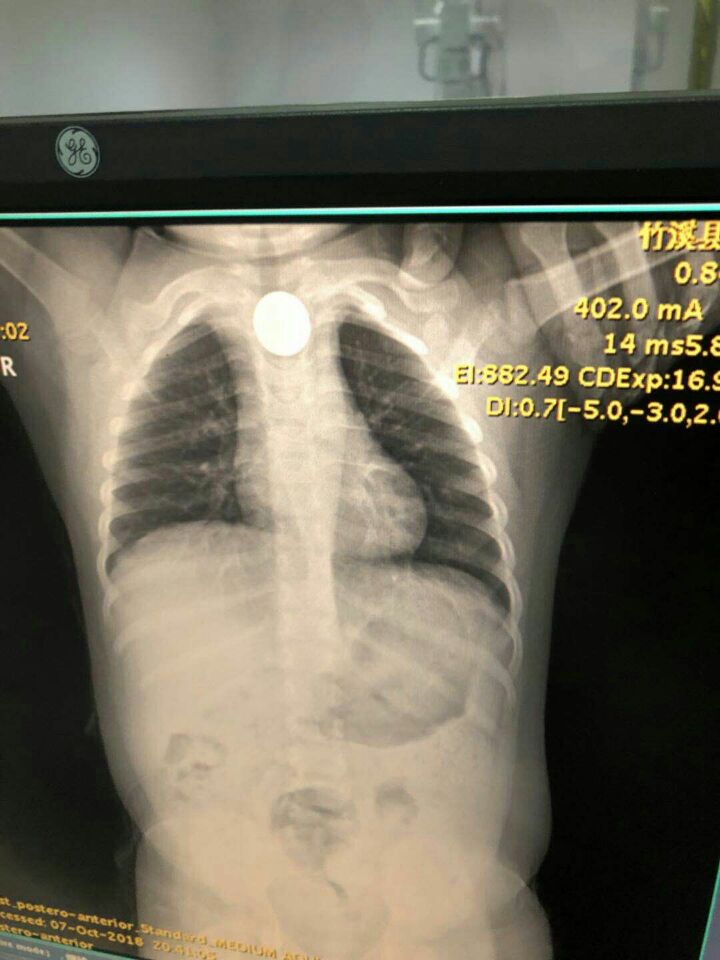

• 都是硬币惹的祸

都是硬币惹的祸

10月7号晚9点,我院同事2岁宝宝在家玩存钱罐不小心把一枚5角硬币误吞入喉中,拍片显示硬币在胸骨后食管第一狭窄处,卡在那里不上不下,情况十分紧急。我和麻醉科黄主任立刻赶往医院,商议取出异物的方案,考虑...

发布时间:2022-03-21